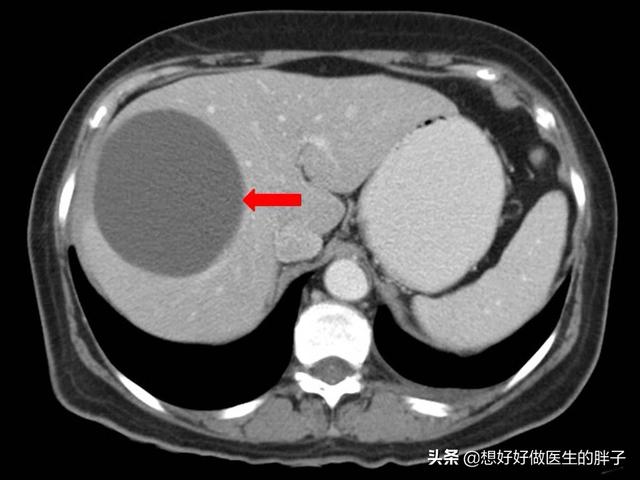

大部分的囊肿对我们的身体并不会产生任何的症状,即使是您体检发现有囊肿,只要不是特别的大,而且不是特别的多,那么就可以忽略不计,不要在心理上老是产生恐惧感,定期体检观察囊肿的变化就可以了。而当一些囊肿长得比较大,对所在的器官造成了挤压,刺激就会产生症状,比如比较大的肝囊肿(下图)。

肝囊肿

这样大的肝囊肿会导致患者出现腹痛,有些患者会表现为胃胀、腹胀,还有些患者会表现出来后背的疼痛,这也是比较常见的症状,因为囊肿对周边造成了比较大的压力,而且很有可能导致患者出现黄疸,如此大的囊肿也面临着破裂的风险,如果一旦破裂,破裂的囊液会流入到腹腔内,而且破裂的囊壁有可能会出血,会造成患者出现难忍的腹痛。对于这样造成比较明显症状的囊肿,无论是肝囊肿或者是肾囊肿,以及身体其他部位的囊肿,只要过大,严重影响患者的功能,可能需要外科手术的干预了。比如通过介入手术或者是穿刺抽吸或者是囊肿切除外科的办法来解决巨大的囊肿问题。